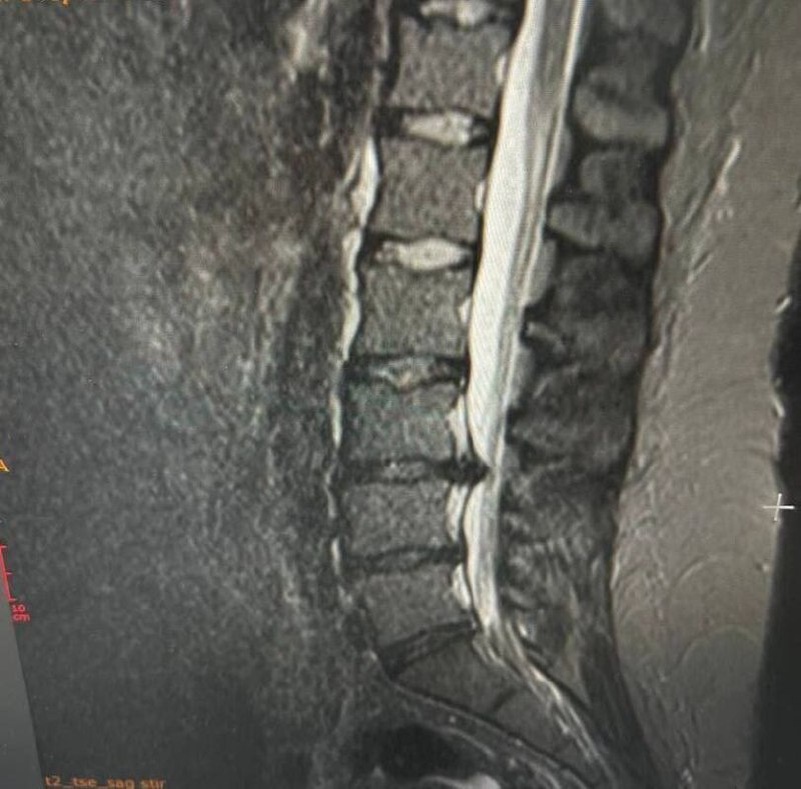

В Истринской больнице врачи Московской области успешно провели операцию на позвоночнике у молодой пациентки с тяжелой грыжей. Крупный фрагмент межпозвоночного диска сдавливал нервные корешки, что ставило под угрозу возможность паралича ног и инвалидности.

Боли в спине мучили девушку более десяти лет, но в последнее время ее состояние значительно ухудшилось: она стала сильно хромать, а обезболивающие препараты перестали действовать.

Врачи быстро провели хирургическое вмешательство, и уже на следующий день пациентка смогла ходить без боли. Сейчас она проходит реабилитацию дома.